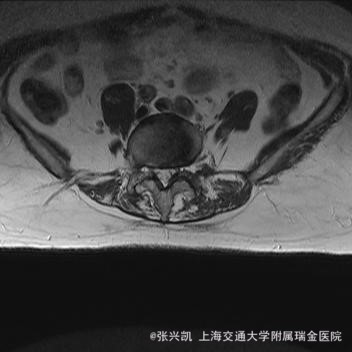

诊断: 腰椎侧弯,腰椎间盘突出 治疗:1期微创侧路椎体融合术+2期 微创后路经皮内固定术

患者侧路微创术后神经压迫症状减轻,腰椎矢状位及冠状位腰椎力线得到改善,戴支具术后可早期下床活动,术后2周后行后路固定手术。